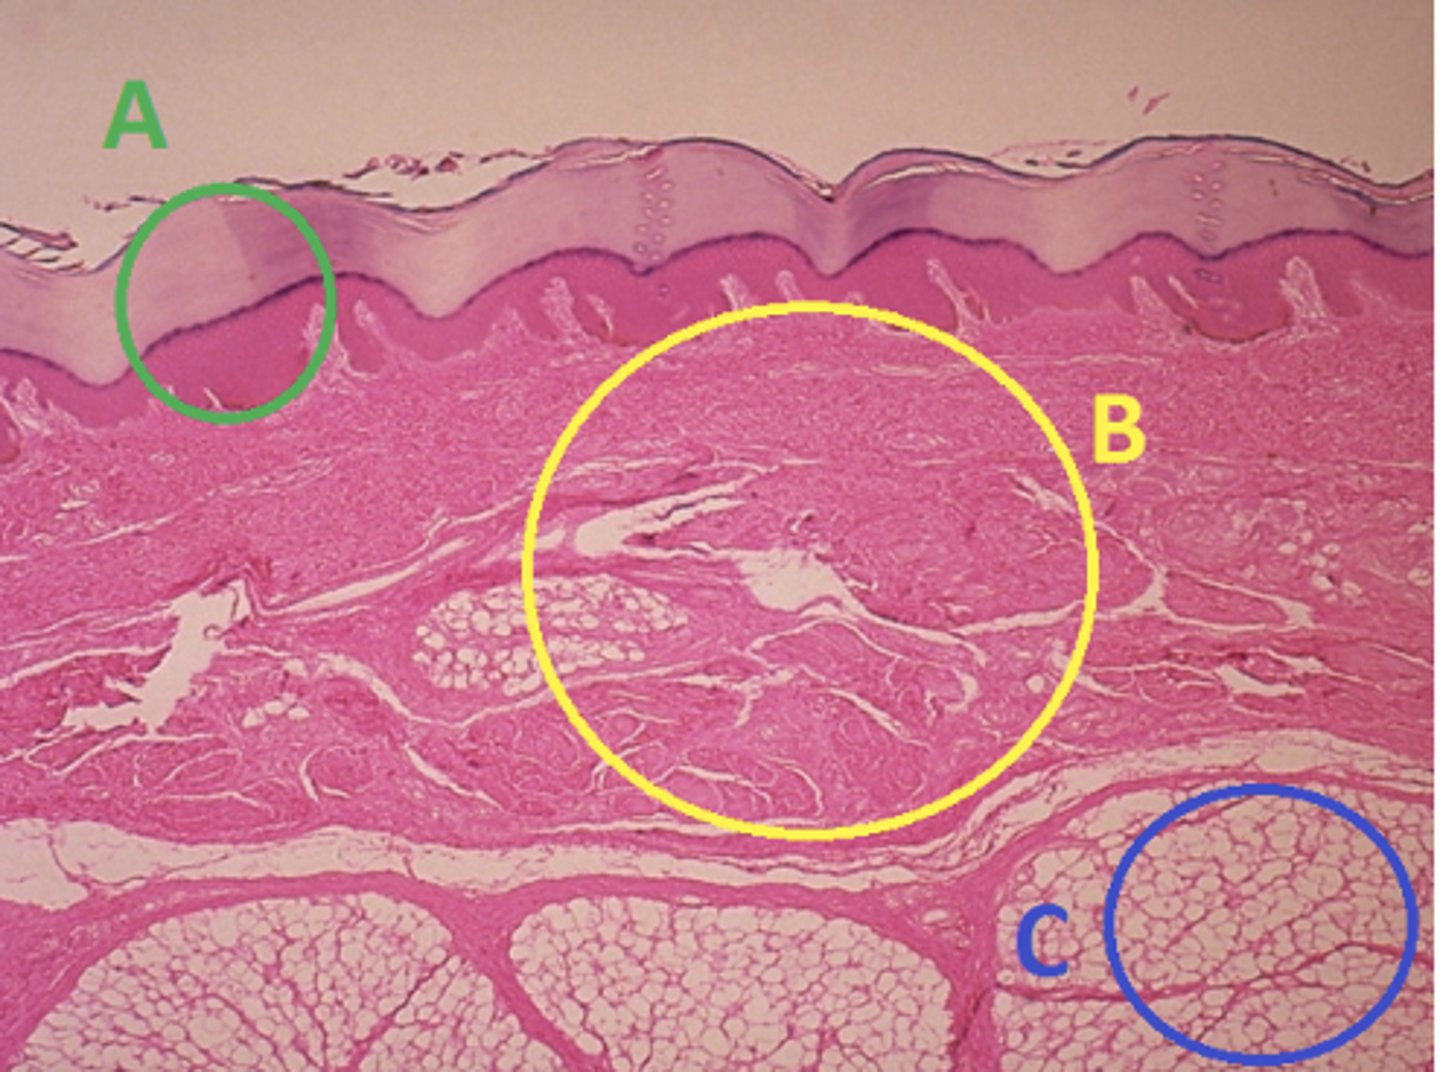

C - hypodermis

Answer the following questions based on the features indicated in the following image. Which letter indicates the administration site for subcutaneous injections?

A - epidermis

Answer the following questions based on the features indicated in the following image. Which letter indicates the administration site for topical creams and ointments?

B - Dermis

Answer the following questions based on the features indicated in the following image. Which letter indicates the administration site for the tuberculin skin test?

A - epidermis

Answer the following questions based on the features indicated in the following image. Which letter indicates a region of the skin with no nerves or blood vessels?

B - Dermis

Answer the following questions based on the features indicated in the following image. Which letter indicates the region where skin appendages (sweat glands, sebaceous glands, and hair follicles) have their roots?

Epithelial tissue

Answer the following questions based on the features indicated in the following image. Which of the four major tissue types is indicated by letter A?

Which letter indicates the administration site for insulin injections?

A

Which letter indicates the administration site for a lidocaine patch?

B

Which letter indicates the administration site for an allergy test?

B

Which letter indicates a region of the skin rich in dense, irregular connective tissue?

C

Which letter indicates the region most important for energy storage and thermal insulation?

Connective

Which of the four major tissue types is indicated by letter C?

Skin of the dorsal surface (back) of the hand

Which part of the body could the previous image represent?

Skin of the ventral surface (palm) of the hand

Skin of the dorsal surface (back) of the hand